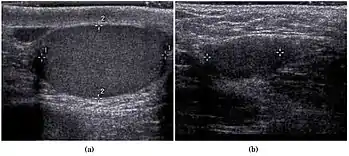

Fig. 27. Varicocele. (a) Multiple tortuous tubular like structure are seen in the left scrotum. (b) Color Doppler sonography shows vascular reflux during Valsalva's maneuver.

Fig. 28. Intratesticular varicocele. (a) Dilated tubular structures are seen within the testis. (b) Presence of vascular reflux is noted during Valsalva's maneuver.

Varicocele refers to abnormal dilatation of the veins of the spermatic cord due to incompetence of valve in the spermatic vein. This results in impaired blood drainage into the spermatic vein when the patient assumes a standing position or during Valsalva's maneuver. Varicoceles are more common on the left side due to the following reasons (a) The left testicular vein is longer; (b) the left testicular vein enters the left renal vein at a right angle; (c) the left testicular artery in some men arches over the left renal vein, thereby compressing it; and (d) the descending colon distended with feces may compress the left testicular vein.

The US appearance of varicocele consists of multiple, hypoechoic, serpiginous, tubular like structures of varying sizes larger than 2 mm in diameter that is usually best visualized superior or lateral to the testis [Fig. 27a]. Color flow and duplex Doppler US optimized for low-flow velocities help confirm the venous flow pattern, with phasic variation and retrograde filling during a Valsalva's maneuver [Fig. 27b]. Intratesticular varicocele may appear as a vague hypoechoic area in the testis or mimics tubular ectasia. With color Doppler, this intratesticular hypoechoic area also showed reflux of vascular flow during Valsalva's maneuver [Fig. 28].